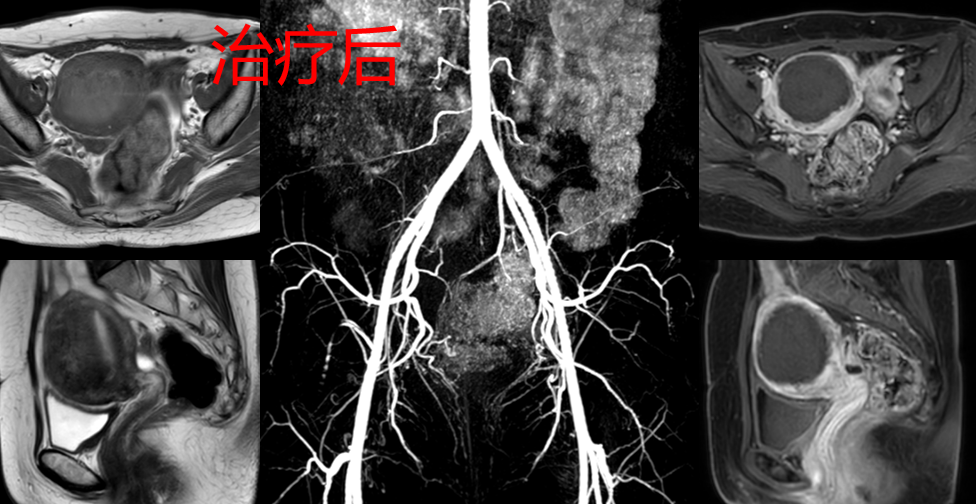

治疗后2个多月曾女士来例假,痛经消失了,月经量较术前明显减少,夜尿消失,可以一觉到天光,睡眠质量杠杠的,精力充沛。3个月后复查磁共振显示:子宫腺肌症完全灭亡(黑色区域),子宫较治疗前明显缩小(如下图)。